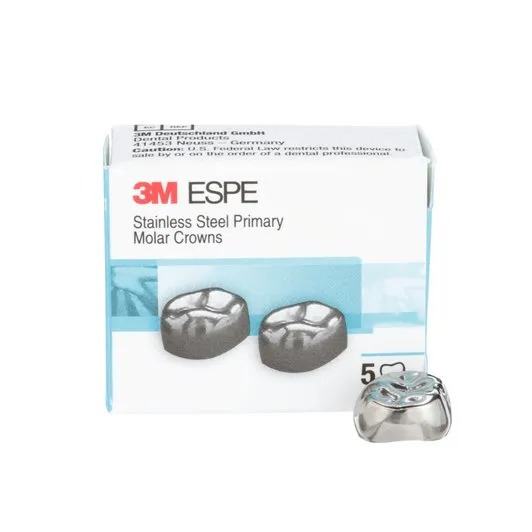

Stainless Steel Primary Molar Crowns for Longevity, and natural anatomy replication for pediatric molars.

Each box of 3M ESPE Stainless Steel Primary Crowns for the 2nd Molar (E) contains a pair of crowns.